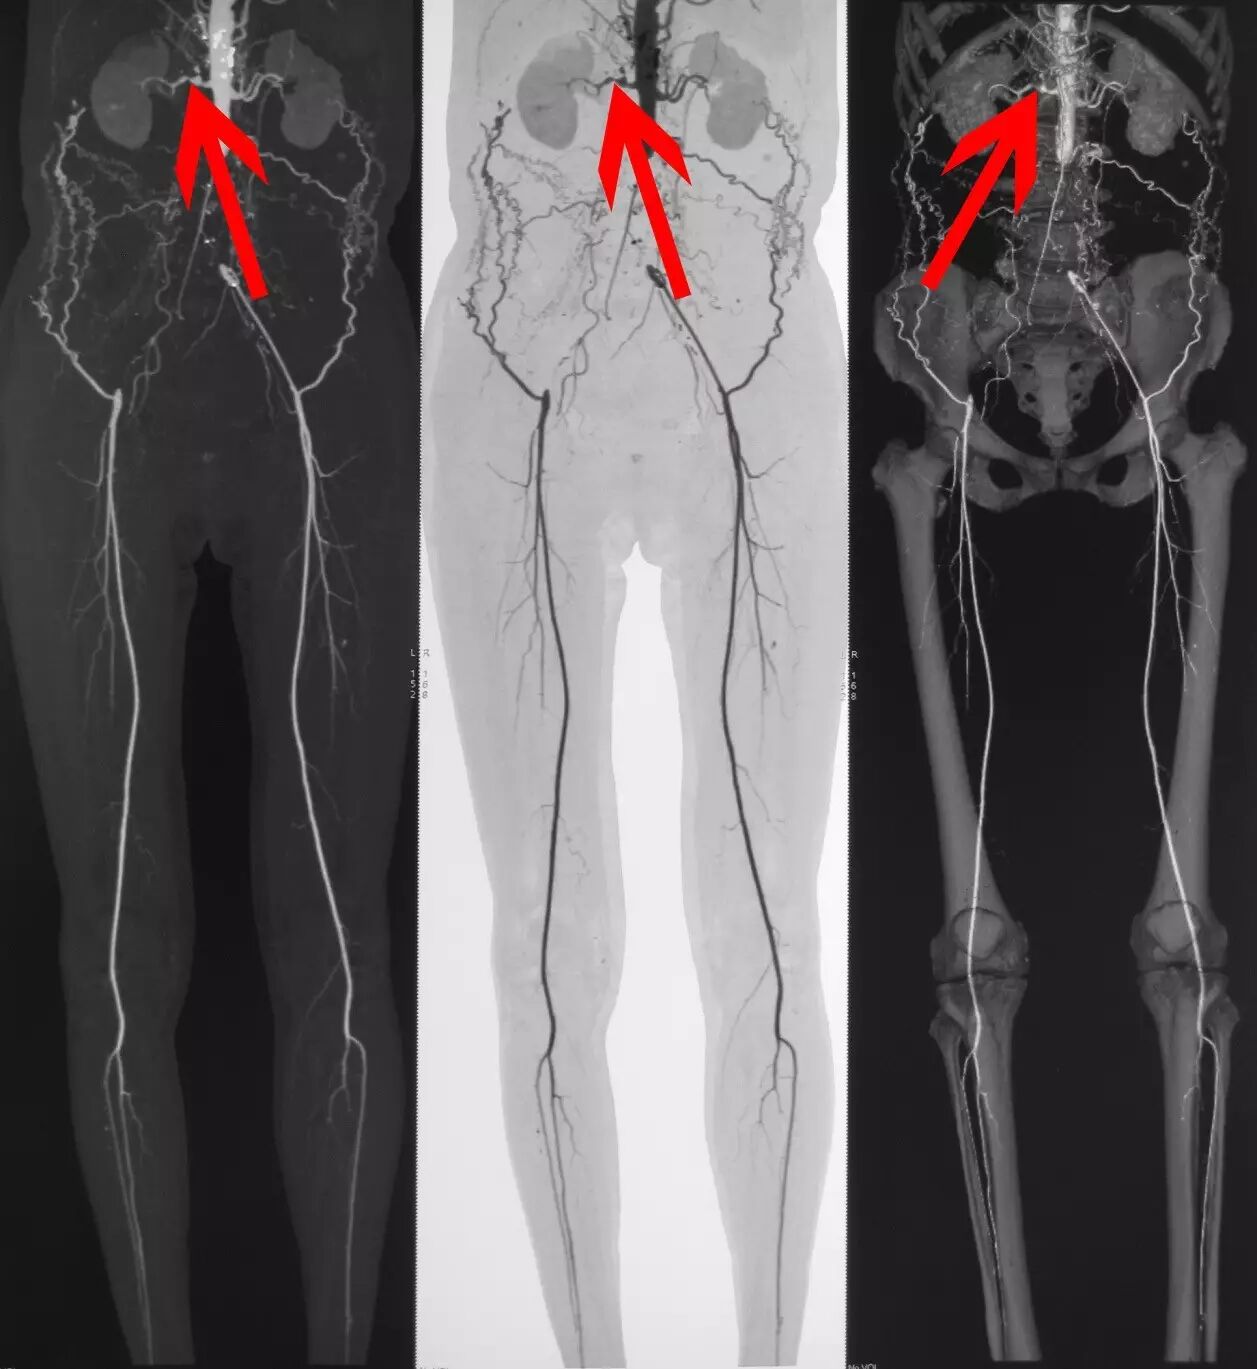

下一步病情评估总体分为两个方面,即动脉炎活动情况评估和全身血管(包括冠状动脉)病变程度的评估,以确定治疗的方向。进一步追问病史,患者出现脑供血不足和肢体缺血表现的2年后于外院诊断为“多发性大动脉炎”,曾口服激素治疗3年(具体用药不详),后因肝功能异常停药,治疗期间基本无发热及症状加重,其后长期服中药,病情也基本稳定,近期无明显发热、食欲不振、关节炎等表现。入院后检查ESR 30mm/h,CRP 0.93mmol/L,综合以上情况考虑多发性大动脉炎处于非活动状态。血管病变的评估方面,患者接受了CT血管造影检查,下肢血管造影结果为(如下图)腹主动脉下段及右侧髂总动脉闭塞,并大量侧枝循环形成;右侧肾动脉中至重度狭窄(箭头所指),左肾动脉轻度狭窄;腹腔干起始部中度狭窄,肠系膜上动脉起始部狭窄。上肢血管造影示双侧锁骨下动脉起始部管腔重度狭窄或闭塞,左侧椎动脉窃血;左侧颈总动脉起始部混合斑块,管腔狭窄40%,左侧颈内动脉闭塞;右侧颈总动脉管腔轻度狭窄;主动脉弓及降主动脉多发低密度斑块及混合斑块,管腔狭窄。

下肢血管造影结果:腹主动脉下段及右侧髂总动脉闭塞,并大量侧枝循环形成;右侧肾动脉中至重度狭窄(箭头所指),左肾动脉轻度狭窄;腹腔干起始部中度狭窄,肠系膜上动脉起始部狭窄。